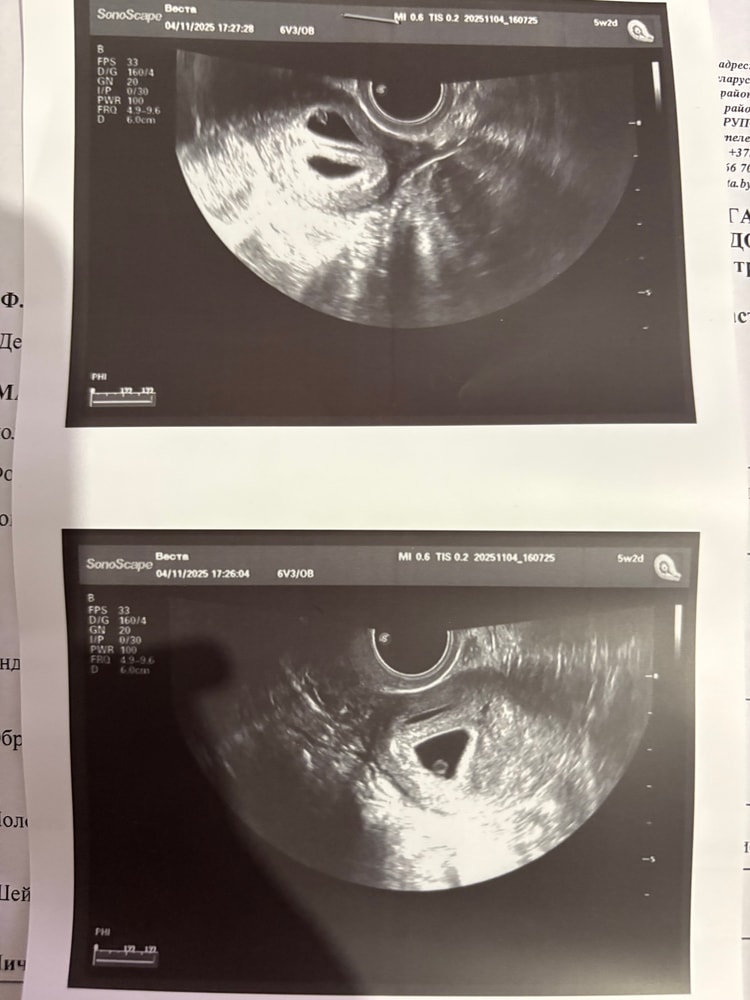

Девочки всем привет,у меня двойня:) такая ситуация. На узи была пару дней назад ,было ровно 7 недель. Не давно мне написала подруга,она была очень рада когда узнала о моей Б,но,она сказала что у нее на 7 неделе уже эмбрион был больше и то что у нее было уже слышно сердечко,а мне сказали что рано еще ((( я стала переживать из за этого,скажите пожалуйста они правда маловаты для 7 недель?(( я просто подумала что это все индивидуально и у нее он был один,а у меня их двое( но загналась ужасно

У вас естественная беременность или эко? В углу снимка у вас стоит срок 5 недель 2 дня. На снимках я вижу только желточные мешочки, что нормально для такого срока. Возможно, была поздняя овуляция

Галчонок, я не знаю почему она поставила 5 недель,когда сказала четко 7. Я сама не поняла этого( беременность естественная

Iskra, по месячным наверное 7 недель у вас, а по размерам крошек больше соответствует 5 неделям и 2 дням. Я думаю, что овуляция поздняя, плюс их двое, а как правильно они поменьше малышей, которые в животике одни) Уверена, что у вас все хорошо)